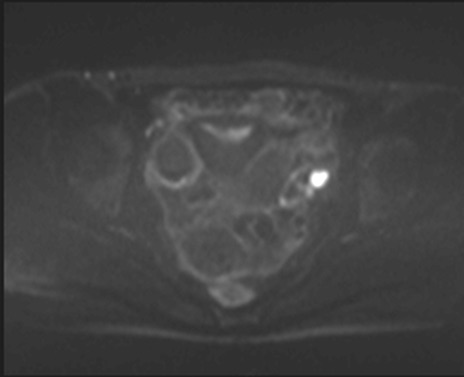

MRI(4日後)